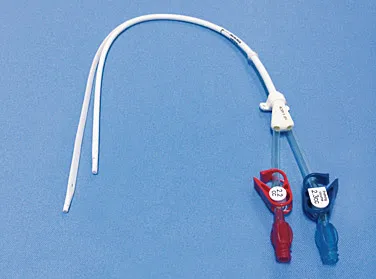

Intoxicação por citrato na contínua: quando suspeitar e como tratar

Intoxicação por citrato na contínua: quando suspeitar e como tratar